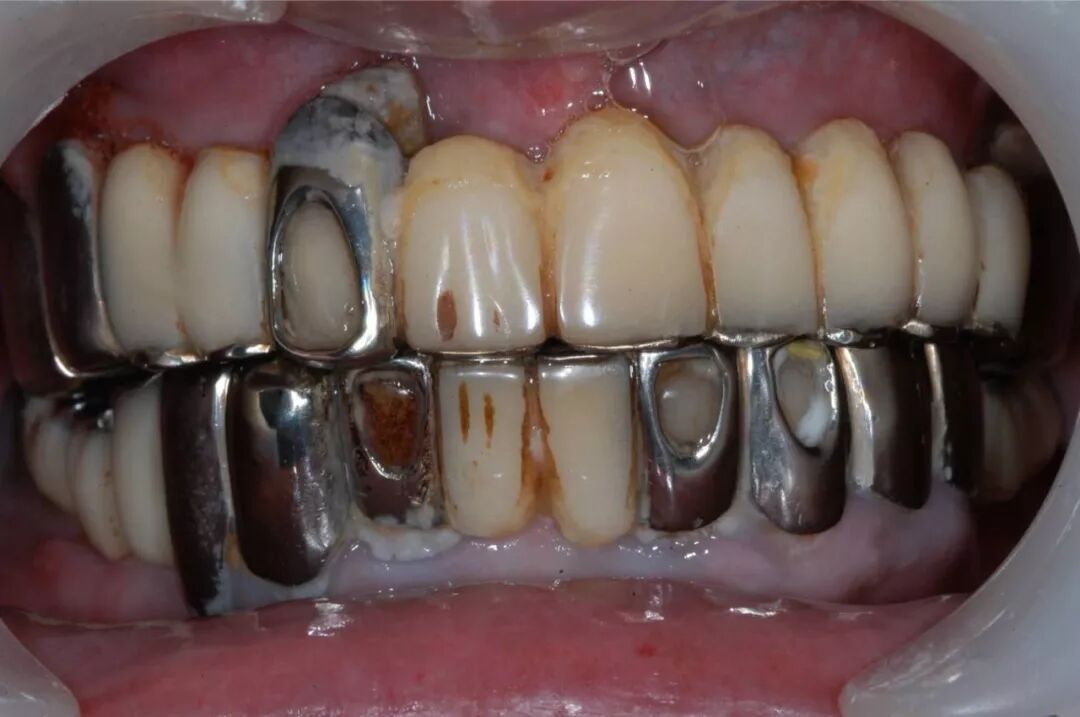

另外,烤瓷桥中的极品——“长江大桥”现象,则是普遍存在于中国各城市各基层牙科的不规范现象,与普通烤瓷桥不同,其本质是一种违反口腔生物力学原理的设计,其最常见的转归是全口牙报废,临床上很多先在基层做,两三年后去医院拆,对口腔健康的影响令人咂舌。

这样的病例实在太多,公立医院和部分高端民营口腔机构每年都要拆除很多例,后续治疗则费时费事费钱费脑筋,而且此类患者来源于社会各阶层,我见过的病例包括一些同事医生(非牙医)的父母,医生的健康意识不代表其家人,而你无法想象其中一例是拥有几百亿资产的企业家,医疗信息不对称应该是主要因素。